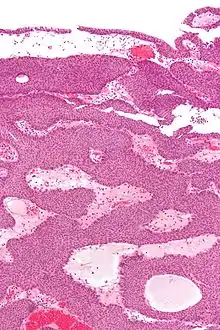

| Micrograph of an inverted papilloma of the urinary bladder. H&E stain. | |

An inverted papilloma, also known as Ringertz tumour,[1] is a type of tumor in which surface epithelial cells grow downward into the underlying supportive tissue. It may occur in the nose and/or sinuses or in the urinary tract (bladder, renal pelvis, ureter, urethra). When it occurs in the nose or sinuses, it may cause symptoms similar to those caused by sinusitis, such as nasal congestion. When it occurs in the urinary tract, it may cause blood in the urine.